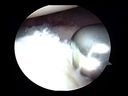

La familia de SutureLasso incluye el SutureLasso original, el SutureLasso de diámetro pequeño, el SutureLasso QuickPass y el MicroSutureLasso; todos estos instrumentos son para un solo uso envasados en forma ésteril. Cada tipo tiene diferentes configuraciones de punta curvas para las reparaciones artroscópicas de Bankart, SLAP y del manguito rotador. El SutureLasso original tiene una punta con un diámetro exterior de 2,3 mm y viene precargado con un lazo de monofilamento de sutura usado para correr la misma a través del tejido blando. El SutureLasso de diámetro pequeño tiene un diámetro en la punta de 1,8 mm y viene precargado con un lazo pasador de Nitinol que se usa para correr la sutura a través del tejido blando. El QuickPass Lasso tiene las mismas dimensiones que el Lasso de diámetro pequeño y tiene ruedecillas para pulgar para avanzar el lazo pasador de Nitinol. Estos dos instrumentos también pueden cargarse con una sutura de monofilamento para transporte o con FiberStick N° 2 para pasar una puntada cuando se usan las anclas PushLock o SwiveLock, con lo que se elimina el paso de transporte.

La punta afilada y el vástago de diámetro pequeño penetran fácilmente en el tejido blando mientras que el vástago reforzado resiste la torsión. Después de pasar la punta por el tejido blando, el lazo se inserta y se recupera a través de una cánula con un gancho de crochet o un recuperador de sutura. Una sutura o extremo de sutura de un ancla colocada anteriormente se pone en el lazo, y el extremo opuesto del lazo se tracciona, de este modo se pasa la sutura por el tejido y se la saca de la cánula.